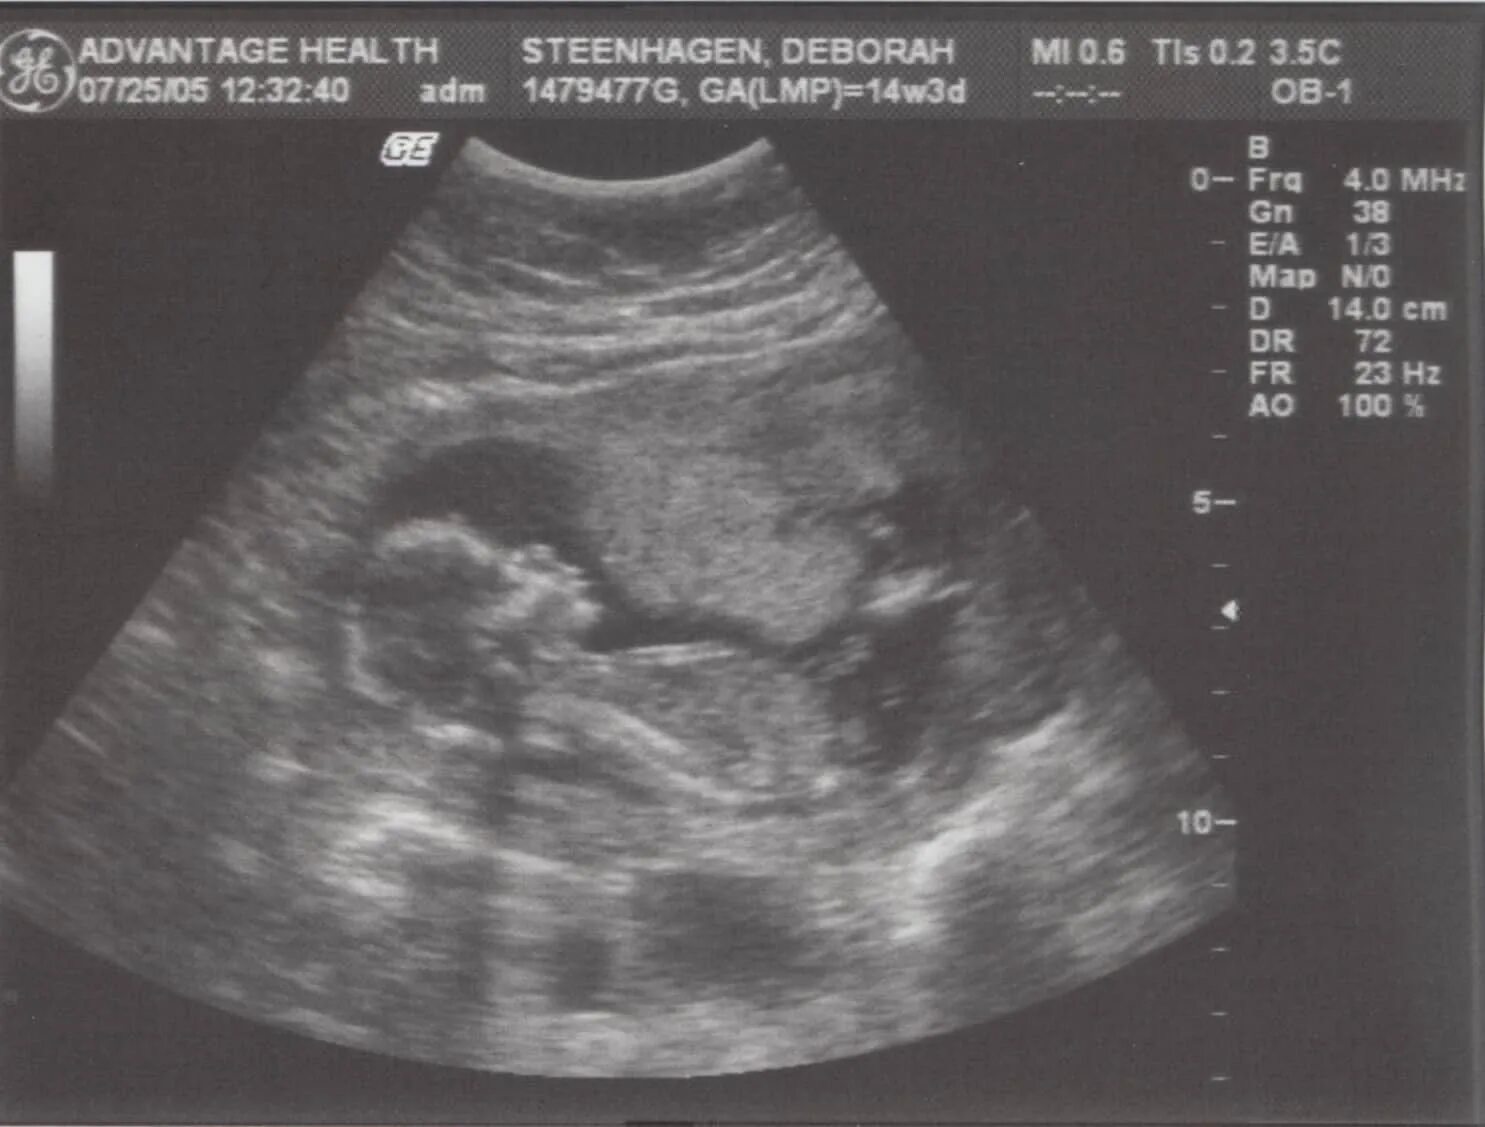

Узи 2 скрининг во сколько недель беременности